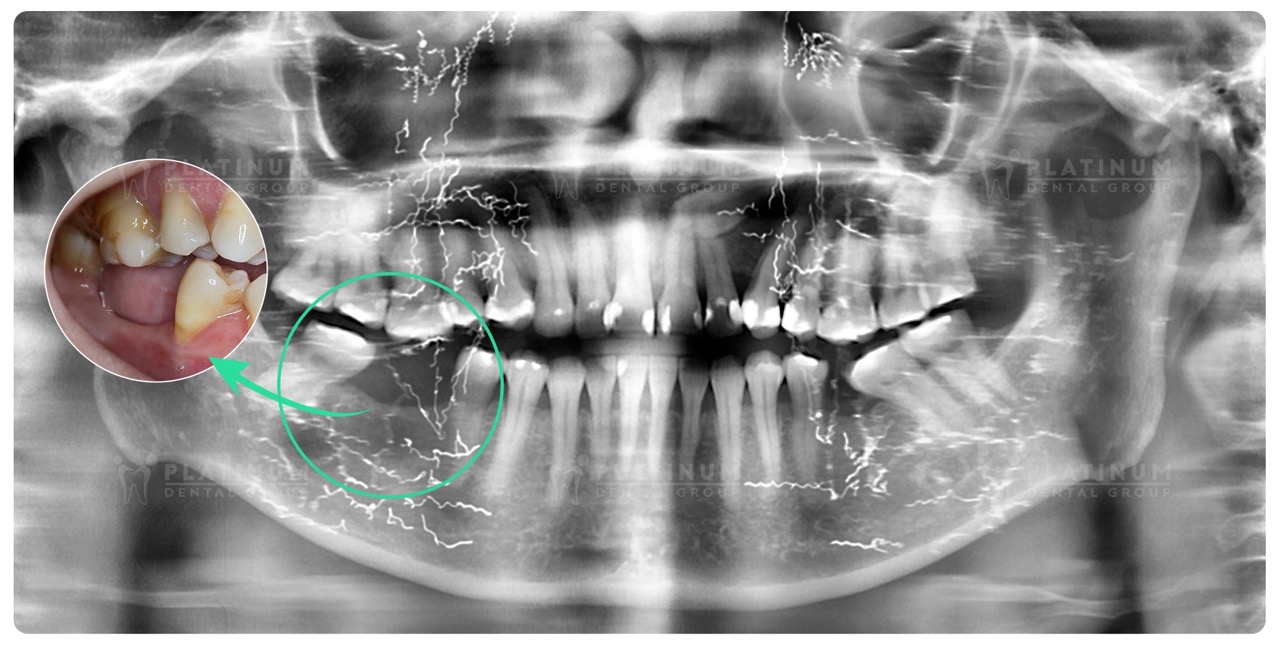

Sau khi thăm khám lâm sàng kỹ lưỡng, đặc biệt là phân tích hình ảnh chuyên sâu bằng máy 3D Conebeam CT, scan răng 3D, bác sĩ Tùng đã tư vấn và lên kế hoạch điều trị, phục hồi hai chiếc răng hàm đã mất cho cô Hà bằng phương pháp Implant đơn lẻ an toàn, hạn chế đau và hồi phục tốt.

- Tình trạng xương hàm đã bị tiêu do mất răng lâu năm, bác sĩ thực hiện ghép xương

- Cấy ghép 2 trụ Implant hàm dưới

- Răng tạm tức thì sau cấy ghép

- Phục hình răng sứ cố định sau 4 tháng chờ trụ tích hợp tốt